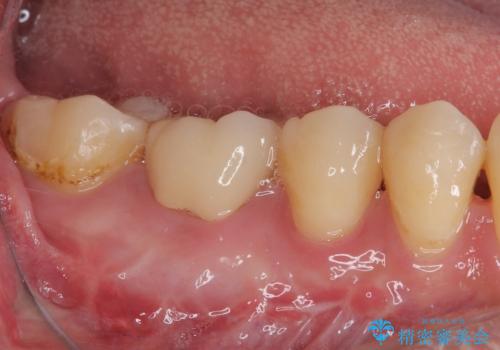

- 他院で矯正治療前後に処置を行った歯が痛むとのことで来院された患者様です。

下顎大臼歯は根管治療がされている歯が咬合時に痛みを感じ、上顎の大臼歯2歯は冷たいものがしみる状態でした。

まずはしみる上顎の歯を仮歯に置き換え、その後下顎の根管治療を行った上で、異常が認められなければオールセラミッククラウンにて補綴治療を行うこととしました。